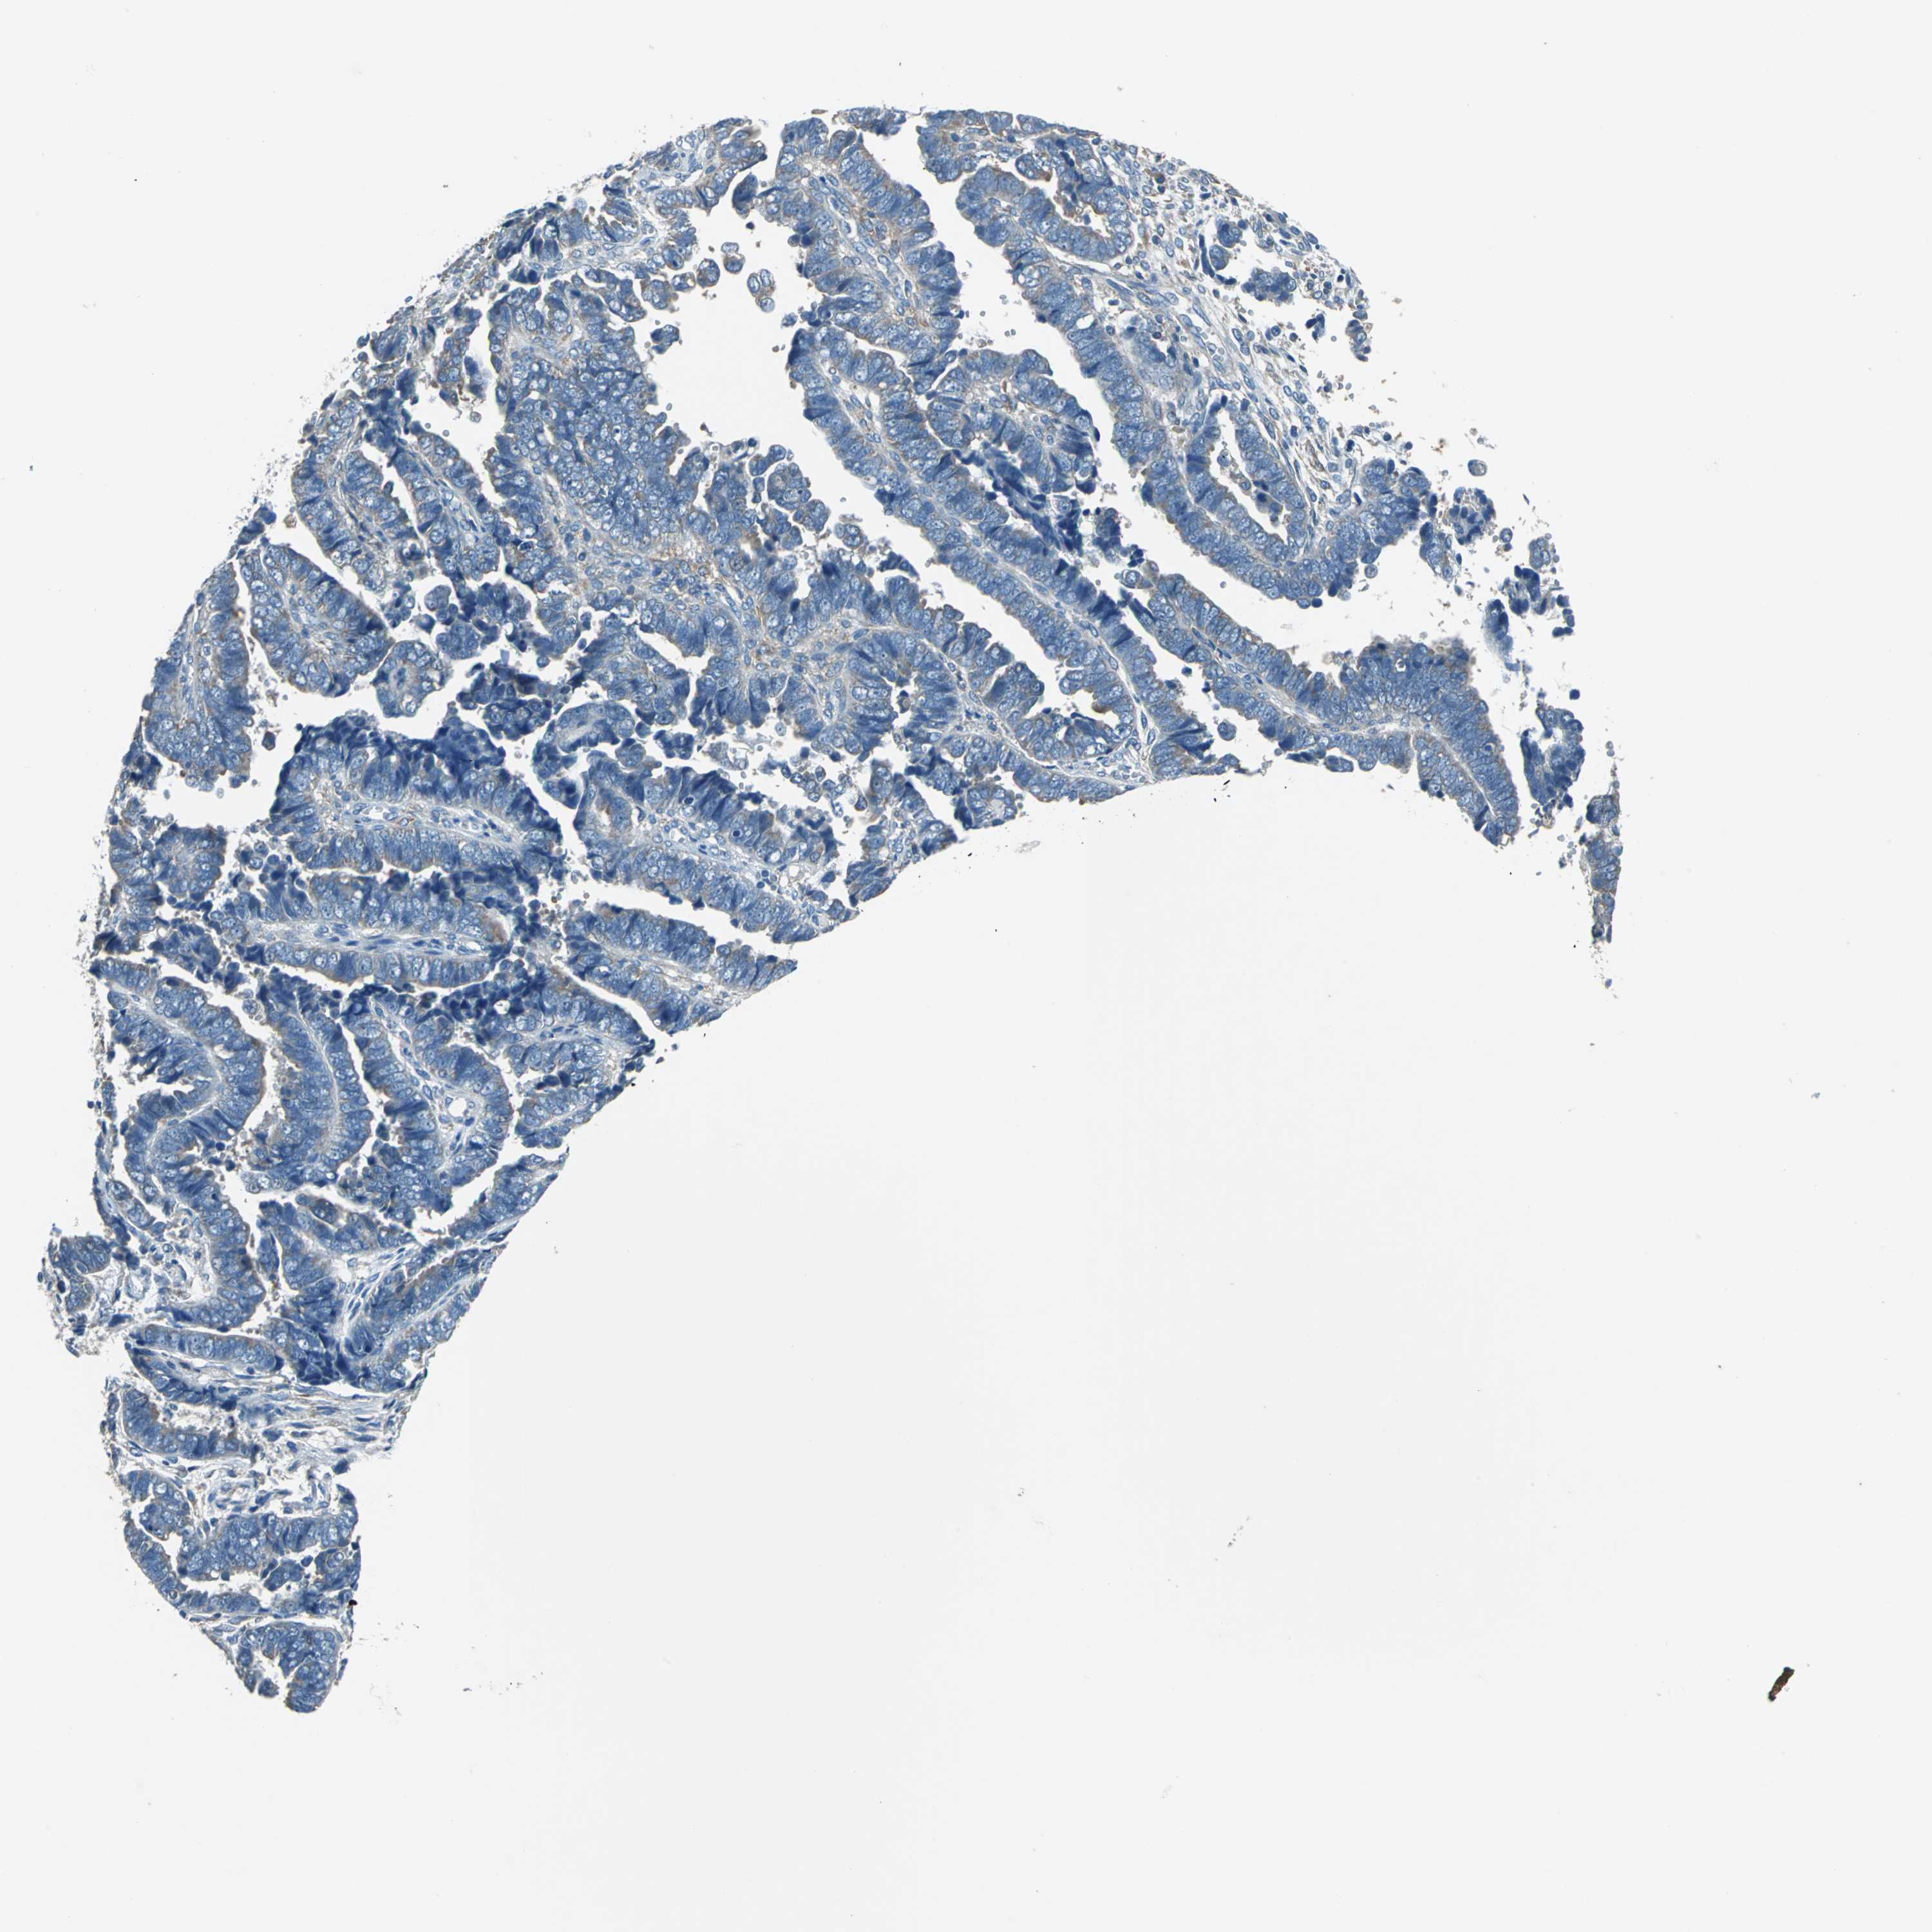

ENDOMETRIAL CANCER - Protein expressioni

A mouse-over function shows sample information and annotation data. Click on an image to view it in a full screen mode. Samples can be filtered based on level of antibody staining by selecting one or several of the following categories: high, medium, low and not detected. The assay and annotation is described here.

Note that samples used for immunohistochemistry by the Human Protein Atlas do not correspond to samples in the TCGA dataset.

Antibody stainingi

Antibody staining in the annotated cell types in the current human tissue is reported as not detected, low, medium, or high, based on conventional immunohistochemistry profiling in selected tissues. This score is based on the combination of the staining intensity and fraction of stained cells.

Each image is clickable and will lead to virtual microscopy that enables deeper exploration of all samples and also displays staining intensity scores, fraction scores and subcellular localization as well as patient and tissue information for each sample.

Antibody HPA006563

Antibody HPA006564

Antibody CAB003844

Antibody CAB016290

Staining

High

Medium

Low

Not detected

Intensity

Strong

Moderate

Weak

Negative

Quantity

>75%

75%-25%

<25%

None

Location

Nuclear

Cytoplasmic/membranous

Cytoplasmic/membranous,nuclear